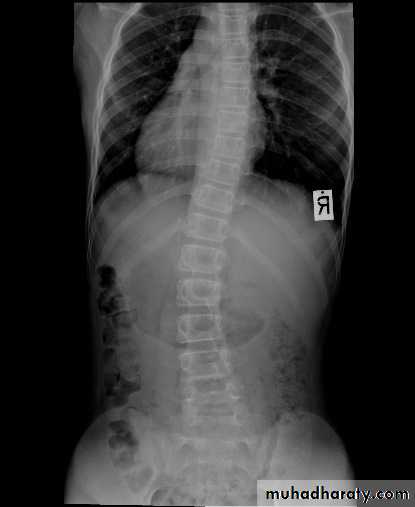

General examinations

ImagingPlain x-rays

AP and lateral views

Oblique views

DEFORMITIES

ScoliosisKyphosis